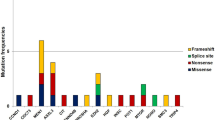

Direct sequence analysis of SDHAF2 in parathyroid tumors

Eighty patients with biochemically proven pHPT due to a single parathyroid adenoma were included in the study to examine whether tumor-specific somatic mutations were present in the SDHAF2 gene. The clinical characteristics of the patients are presented in Table 1. Automated sequencing of all coding regions identified an annotated SNP, rs879647 (A to G substitution in intron 2) in 9/80 parathyroid tumors, as well as in the germline DNA of these patients (Fig. 2). The frequency with which the various alleles were observed was as follows, the G allele was observed in 0.127 of the patients which is not significantly different from the 0.161 allele frequency reported in the HapMap CEU European cohort of 112 individuals (http://www.ncbi.nlm.nih.gov/projects/SNP/snp_ref.cgi?rs=879647). Similarly, the A allele had a similar observed frequency of 0.873 compared to 0.839 in the HapMap CEU European cohort (non significant). No tumor-specific somatic mutational aberrations, such as nonsense, frameshift, or other inactivating mutations were identified.